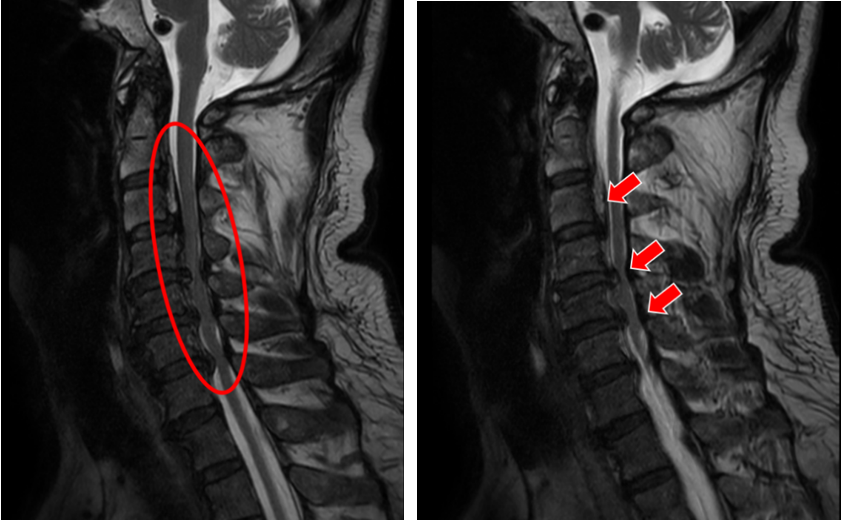

(姐姐的颈椎CT显示她的颈椎椎体同样存在明显的后纵韧带骨化,与弟弟不同的是,她的韧带骨化程度更严重)

就在吕飞出院的当天,另一位症状相似的脊髓型颈椎病患者吕艳也来办理了住院手续。原来她是吕飞的亲姐姐,今年46岁。姐弟俩的症状和影像学表现都几乎相同,可见颈椎后纵韧带骨化确有一定的家族遗传倾向。吕艳告诉我们,他们姐弟这些年看过不少医生,都建议尽早手术,但因为听说颈椎手术风险极高,所以一直都选择“拖字诀”处理。这次吕飞的手术效果,给了她极大的信心和勇气,她毫不犹豫地也选择来做手术。

(颈椎MRI提示C2-6椎管狭窄,脊髓受压严重)